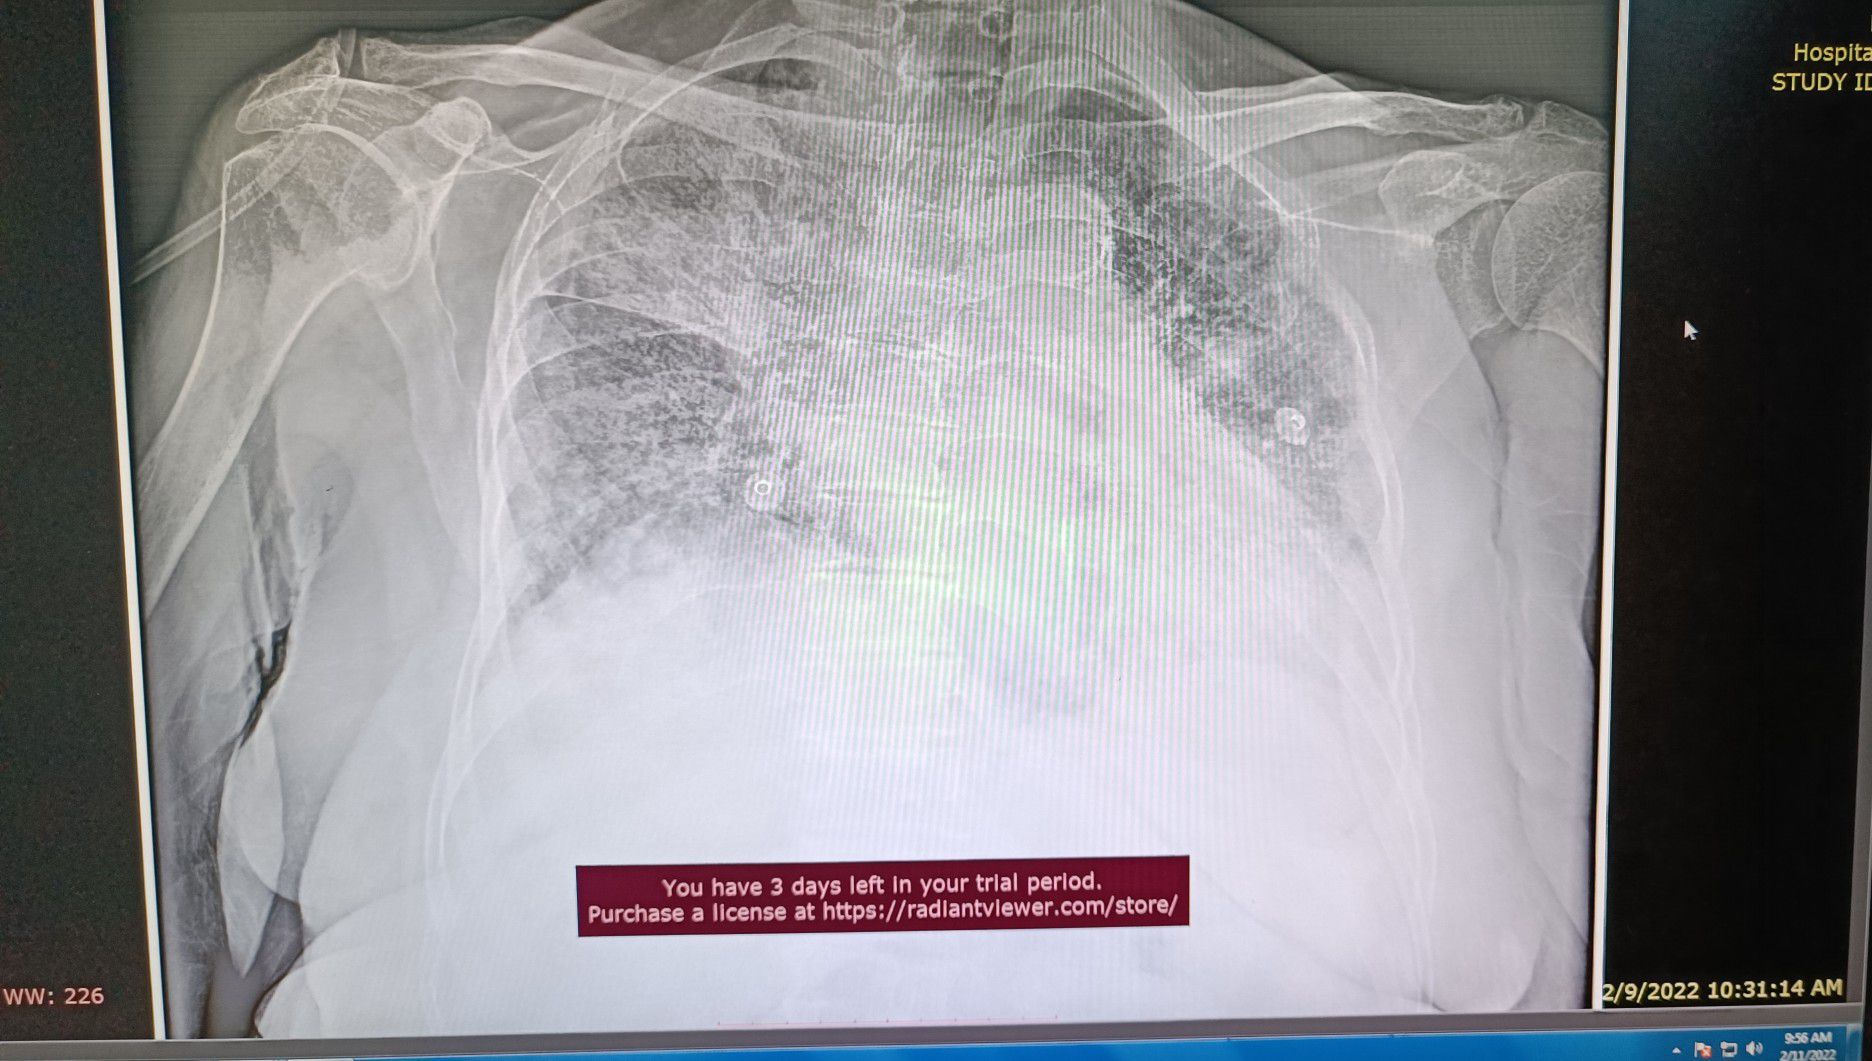

Patient with CPAP mask SPO2 90% FiO2 100%.

Covid19

Mask

Cpap